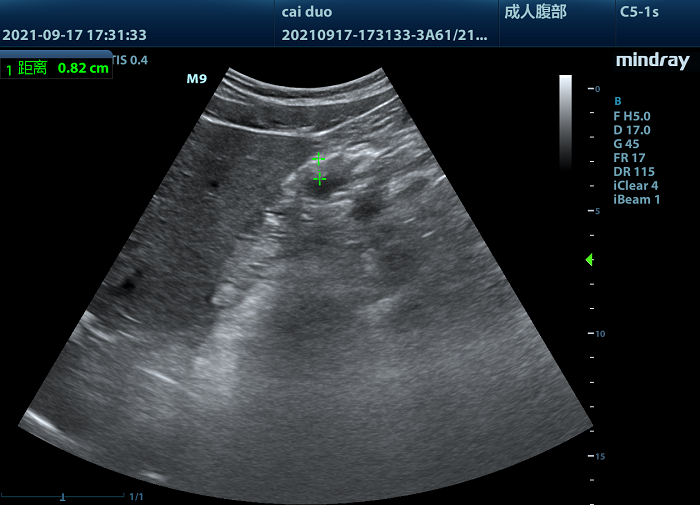

事出9月下旬,林芝市人民醫(yī)院重癥醫(yī)學(xué)科經(jīng)綠色通道接收了一名57歲急性重型腦挫傷的男性患者,經(jīng)過重癥醫(yī)護團隊的一系列救治,終于將患者從死亡線上拉了回來。由于該患者顱腦損傷嚴重,呼吸衰竭,需要有創(chuàng)機械通氣,并行鼻胃管腸內(nèi)營養(yǎng)支持治療。但患者在行鼻胃管腸內(nèi)營養(yǎng)時,已經(jīng)出現(xiàn)嚴重不耐受情況,單次胃潴留明顯,誤吸風(fēng)險大,營養(yǎng)補給問題成為目前必須解決的問題。超聲查看患者胃竇情況,顯示胃壁明顯增厚(圖1),胃竇輪廓不清晰。

(圖1)